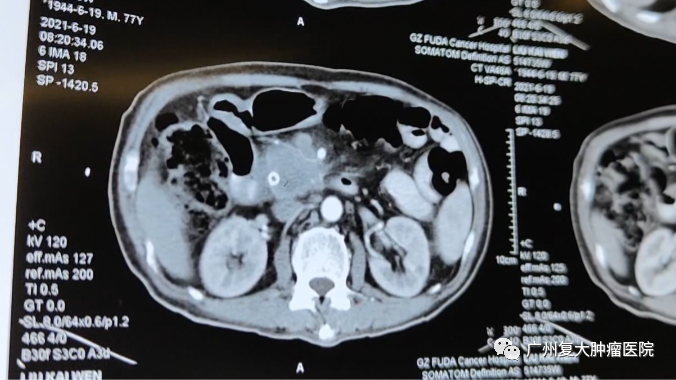

CT图片

为求进一步治疗,刘叔来到我院就诊。入院后刘叔完善相关检查,其彩超检查显示胰头部有大小约5.1×4.9×3.0cm低回声肿物、肝脏多发转移瘤。由于胰头肿物不仅累及相邻门静脉并压迫胆总管下端致胆总管、肝总管、胆囊管及肝内外胆管扩张,还浸润周围脂肪间隙,胰腺体尾部萎缩;同时检查发现刘叔存在轻微房颤的症状,无法实行根治性手术。